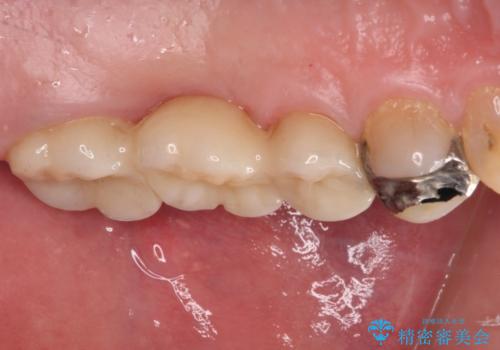

上顎の歯根のみとなった歯は抜歯が必要であったので、抜歯を行い、インプラントあるいはブリッジのよる補綴治療を提案しました。

前後の歯は銀歯が装着されていたため、ブリッジによる補綴治療として、前後の歯もセラミックに置き換えることとしました。